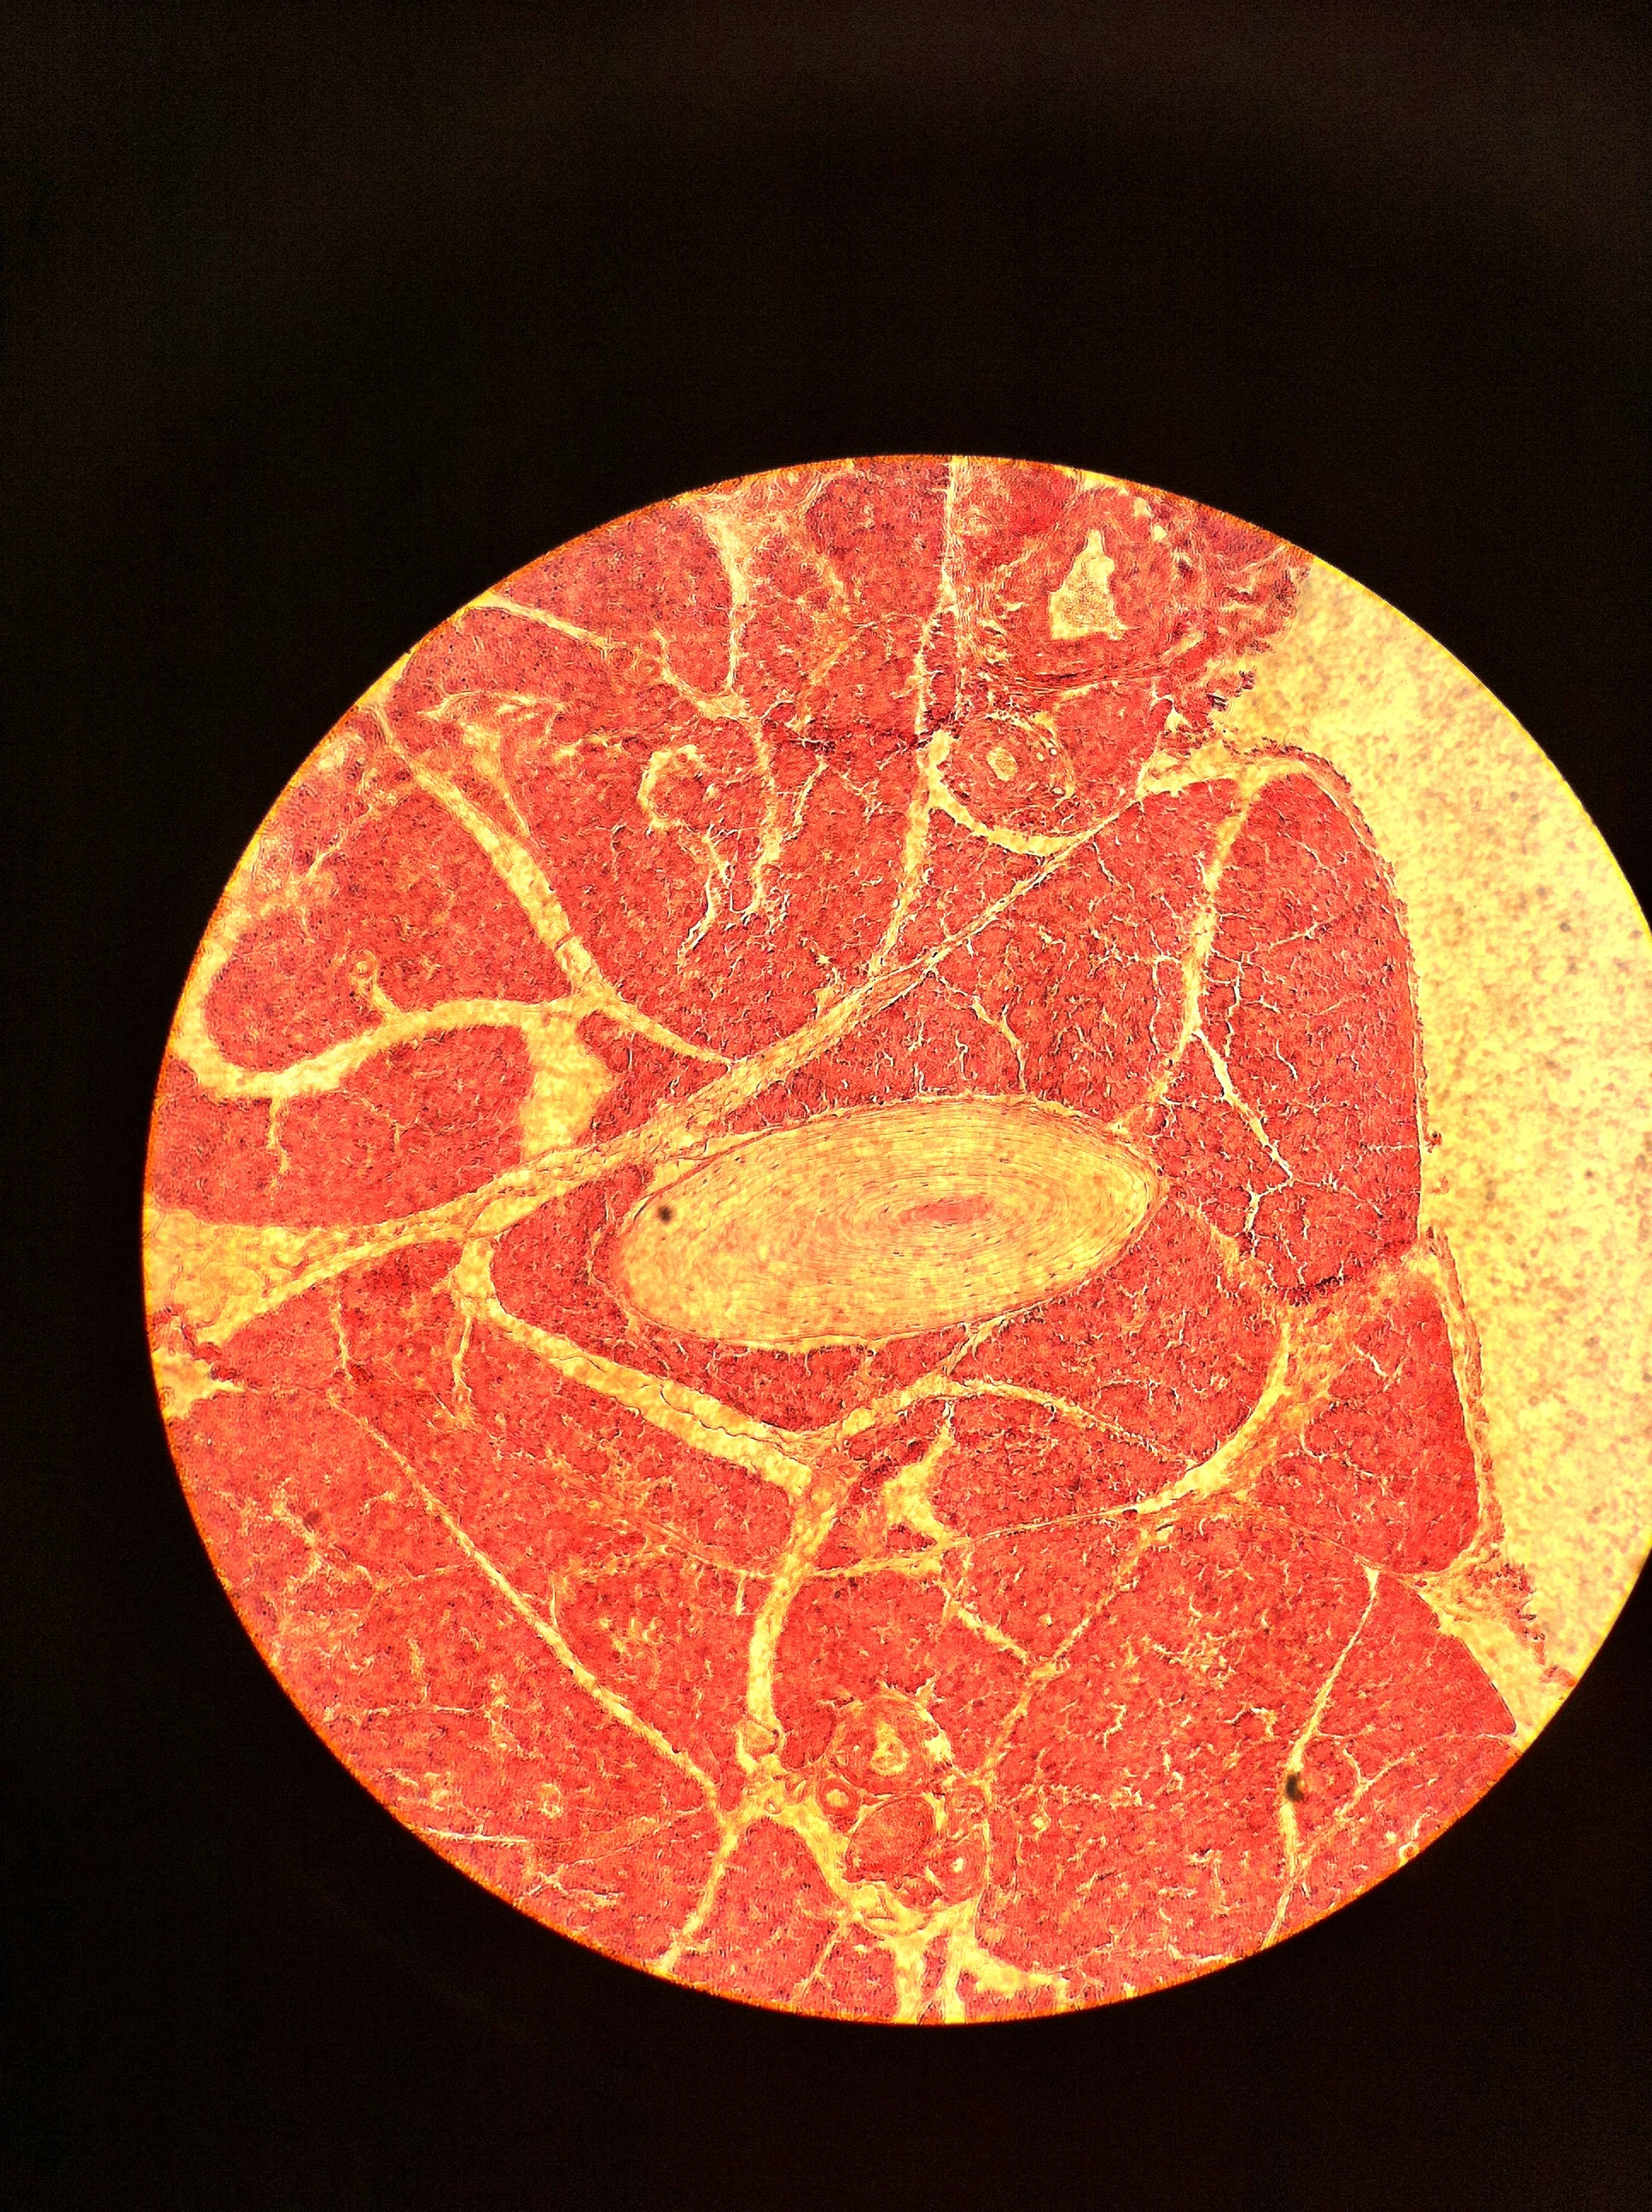

Pacinian Corpuscle 100X